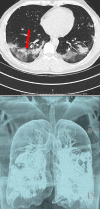

Effectiveness of Computed Tomography in the Diagnosis of Novel Coronavirus-2019

Coronaviruses (CoV) belong to the coronavirus genus of the coronaviridae family. All CoVs are pleomorphic RNA viruses containing crown-like peplomers of 80-160 nm in size. This virus is a zoonotic pathogen seen with a wide range of clinical features from asymptomatic state to intensive care in humans. So far, seven human coronaviruses have been identified with the last one being Coronavirus-2019 (COVID-19). These pathogens typically lead to mild disease, but SARS and MERS type coronaviruses have caused severe respiratory disease and even mortality within the last 20 years. COVID-19 virus has rapidly spread worldwide after China and is continuing to cause huge economical and social impacts. Given the scarcity of resources including healthcare staff, hospital capacities, test kits, etc., timely diagnosis and treatment of this virus are of paramount importance. However, there is no vaccination or drug developed for the treatment of this disease up to today. Because the spreading rate of the virus is very high worldwide and there is no definitive treatment, diagnosis becomes even more important. The objective of this review is to evaluate the use of chest computed tomography, one of the commonly used radiologic imaging modalities, in the diagnosis of COVID-19 in light with the current literatüre.